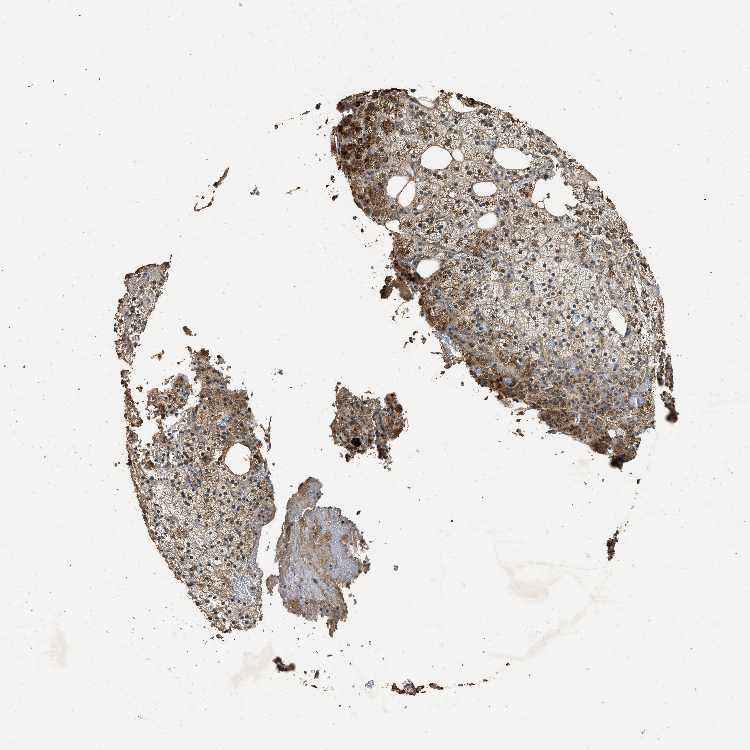

ADRENAL GLAND - Antibody stainingi

Antibody staining in the annotated cell types in the current human tissue is reported as not detected, low, medium, or high, based on conventional immunohistochemistry profiling in selected tissues. This score is based on the combination of the staining intensity and fraction of stained cells.

Each image is clickable and will lead to virtual microscopy that enables deeper exploration of all samples and also displays staining intensity scores, fraction scores and subcellular localization as well as patient and tissue information for each sample.

Antibody HPA019100Antibody CAB037044

Glandular cells MediumMedium